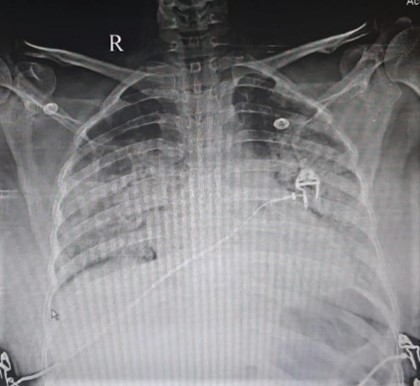

X-Ray